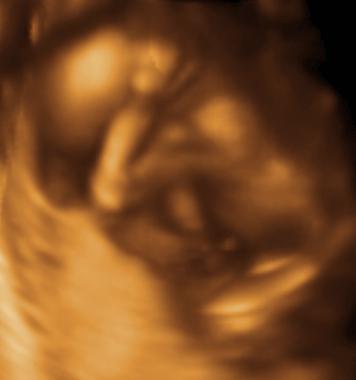

Last night Pablo and I had to run to Labor and Delivery at the hospital for some tests due to some unexpected (and slightly profuse) bleeding. All tests checked out normal, and Rory is fine (no placental abruption or anything like that), although the med staff couldn't tell us what would have caused the bleeding, so we're left answer-less. We did get a new ultrasound photo, though, so take a look. She's due in exactly 2 months (but measuring big, so maybe she'll come a little early? I've still only gained 5 lbs since November (yay!) so I'm feeling pretty good, all things considered.

This is the same Ultrasound partially colorized to help you see her better

hips <---------------------------> head

looking stright toward you

Our 3 D photos as the baby looks away, hides her face, etc. We finally got a photo where the umbilical cord isn't right in her face, and she put her arms up!...

See... she's looking right out at you! Nifty, huh?